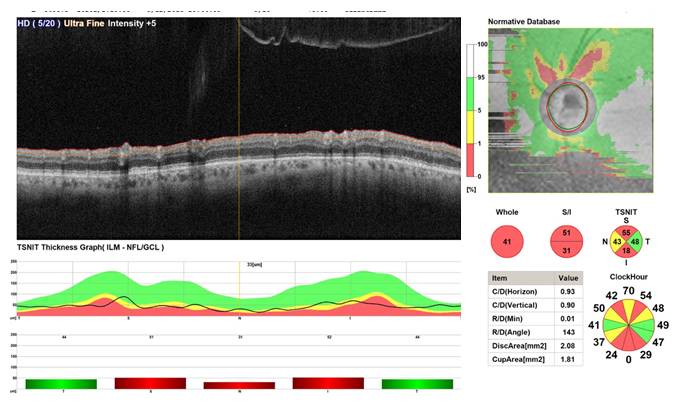

The OCT of the optic disc in map and circle scans shows reduction of ganglion cell complex volume along with reduction of RNFL thickness in superior, inferior, and nasal to the optic disc.

OCT of the optic disc map and circle shows no significant changes in term of ganglion cell volume and thickness of the RNFL (Figure 3).

Figure 3 Shows OCT scans every 4weeks of the optic nerve and RNFL from baseline toward 8weeks follow up showing no significant changes.